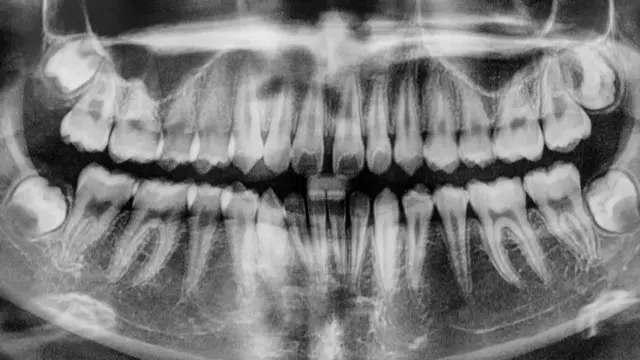

Когда же наконец зубной врач сможет вырастить нам новый зуб?

Обозреватель BBC Future рассказывает о щадящих и эффективных методах лечения зубов, которые позволят забыть о боли в кабинете стоматолога.

Зубы разные нужны, зубы всякие важны

Может показаться, что в сравнении с другими животными человеку очень не повезло иметь один и тот же набор постоянных зубов на протяжении почти всей жизни.

Так почему же, если у акул, равно как и у многих рептилий и амфибий, зубы могут отрастать неограниченное количество раз, у человека они сменяются лишь однажды?

Эбигейл Такер, профессор в области развития и эволюции из Королевского колледжа Лондона, говорит, что между сложностью строения зубов и их способностью отрастать заново существует обратная взаимосвязь.

Поскольку млекопитающие умеют жевать, то есть измельчать пищу, двигая челюстями из стороны в сторону (особенно ярко это заметно на примере жевательных движений коров и лошадей), их зубы имеют сложное строение, а форма зубов определяется наличием на них бугорков.

Так, на клыках всего один бугорок, на премолярах (малых коренных зубах) - по два, а на молярах (коренных зубах) - по четыре или пять бугорков.

У большинства млекопитающих зубы сменяются только раз в жизни - на месте молочных вырастают постоянные. Тем не менее, у некоторых видов млекопитающих сохранилась (или вновь развилась) способность к регенерации зубов.